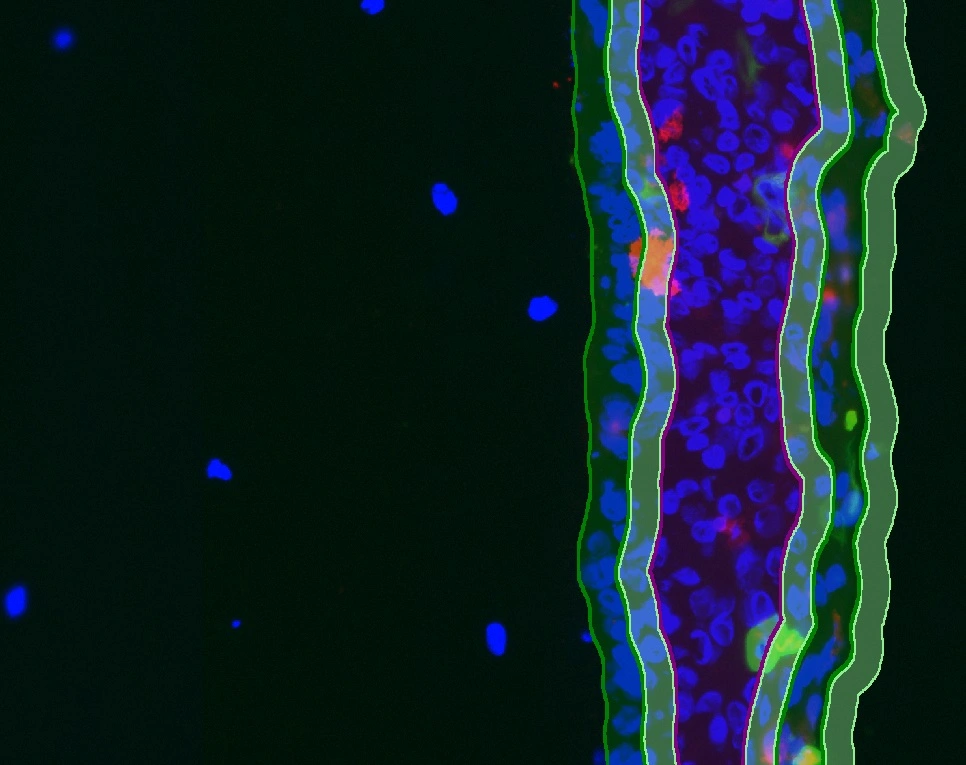

New StrataQuest App: IF ARTIFICIAL SKIN

The IF Artificial Skin App stratifies skin equivalents into dermis and epidermis, further dividing the epidermis into stratum corneum, suprabasal, and basal layers. It outputs area, mean staining intensity, nuclei counts, and % of marker-positive cells for each layer and sublayer. Read publication here